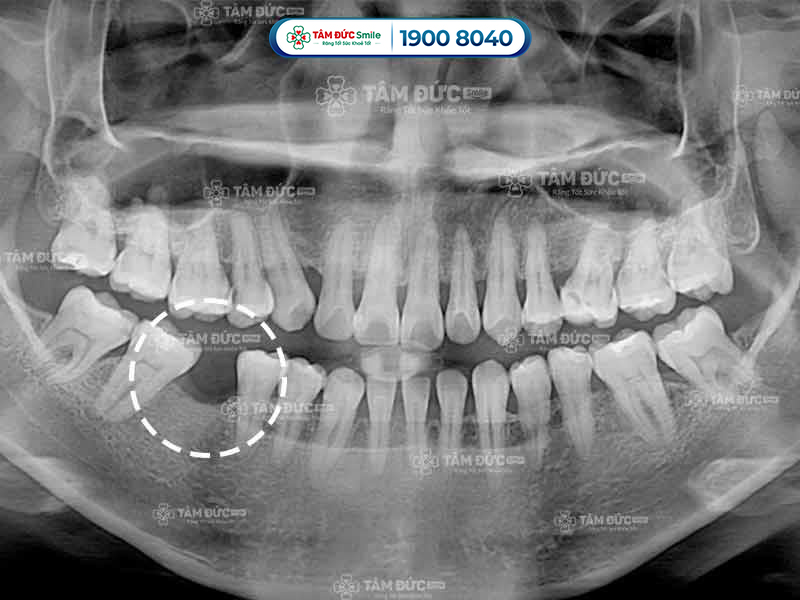

10.2. Bước 2 - Chụp phim CT Cone Beam và làm các xét nghiệm

Ngoài chụp phim CT, Quý khách còn được làm 1 số xét nghiệm cần thiết để đánh giá sức khỏe có đủ điều kiện trồng răng Implant hay không. Khi có đủ các kết quả kiểm tra, bác sĩ bắt đầu xây dựng phác đồ điều trị phù hợp.

- Kiểm tra chất lượng xương hàm trước khi trồng răng bằng cách chụp phim CT.

Trụ Implant kém chất lượng sẽ nhanh chóng bị cơ thể đào thải ra ngoài, làm Quý khách bị chảy máu chân răng hoặc viêm nướu. Kết quả chụp phim X-Quang cho thấy xương không bám vào trụ Implant, lúc này Quý khách cần phải trồng răng lại từ đầu.